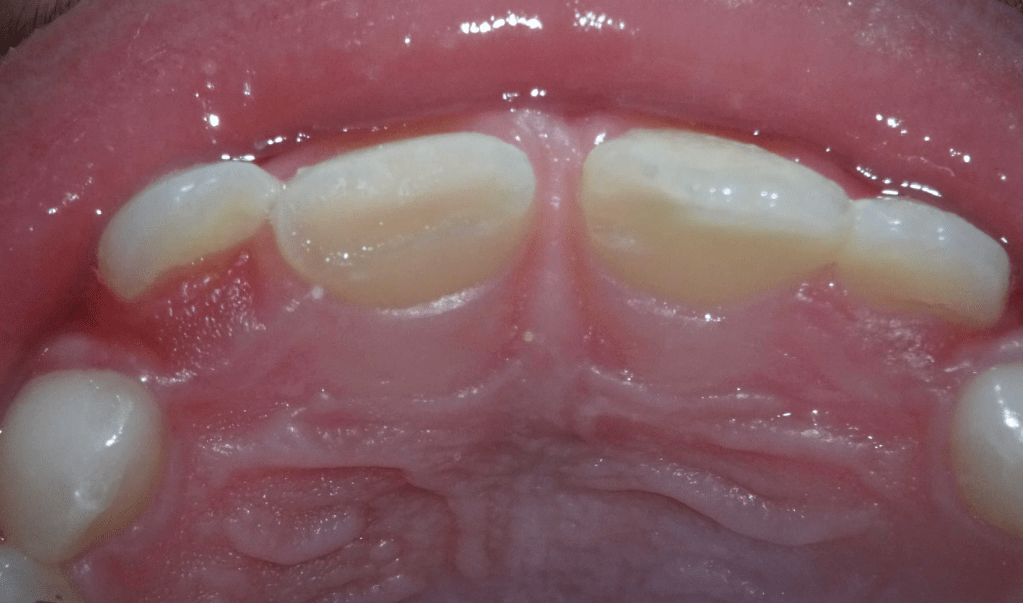

Reco palatina